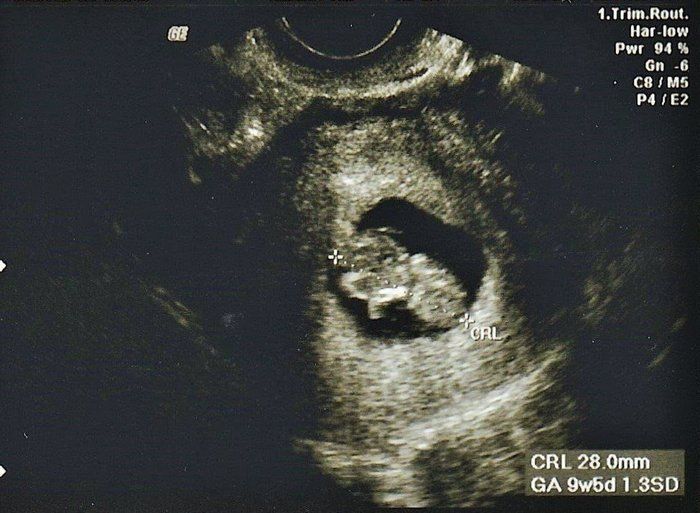

小吉さんの妊娠9週目のエコー写真

赤ちゃんは2.8cmになりました。ハート型のように写っている胎嚢の右側にあるのが頭で左側が体です。人間らしくなってきたのが嬉しかったのを覚えています。マクロビオティックの先生からいただいたアドバイスを元に、食事内容や体を冷やさないことなどに注意をしながら慎重に毎日を過ごしていました。